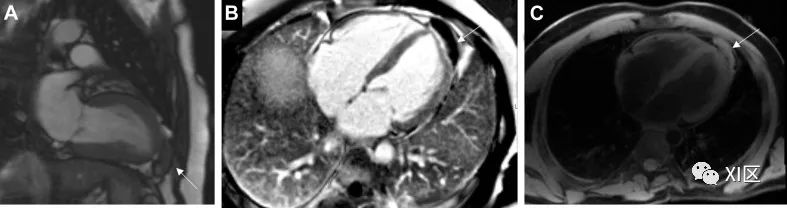

心黏液瘤(图 2)是最常见的 PCT,据信来源于间充质细胞前体。它们形成腔内肿块,最常见于左心房,通过柄与卵圆窝相连,但也可能出现在儿童的右心房。其他解剖学来源包括心房游离壁和二尖瓣瓣叶;但这些来源的可能性较小。有 7% 的患者在就诊时被发现患有心脏黏液瘤,与卡尼综合征(一种多发性肿瘤和皮损综合征)有关联。确诊时的平均年龄为 50 岁,约 70% 的患者为女性。

图 2 黏液瘤53 岁男性,左心房黏液瘤,曾出现栓塞事件。(A)经胸超声心动图检查发现附着在房间隔上的巨大移动肿块(白色箭头)。(B)心脏CT中看到的表面光滑的低衰减、轮廓清晰的肿块(黑箭头)。C)CMR晚期钆成像中左心房肿块的异质摄取(白箭头)。

在超声心动图检查中,心脏黏液瘤通常表现为一个移动的肿块,通过一个柄附着在心内膜表面,通常从卵圆窝产生。RT3DE 可通过裁剪功能和仔细使用数字分析来剖析病灶,从而帮助进行梗阻分析和肿块异质性分析。可能需要进行 TEE 检查,以更好地观察植入部位,并确定是否有可能扩展到肺静脉或腔静脉。在心脏 CT 上,黏液瘤通常表现为腔内低衰减肿块,表面光滑或略带绒毛。约 14% 的患者可见钙化,右侧病变更常见。动脉期造影剂强化通常不存在,但在较长的时间延迟下进行的检查中可发现异质强化。电影图像的重建有助于评估病变的移动性和附着情况;但这往往并不可靠,尤其是对于茎干较短的肿瘤。在 CMR 上,T1 和 T2 加权图像上通常会出现异质外观,这是由于黏液瘤的成分所致,黏液瘤往往含有不同数量的黏液组织、出血组织、骨化组织和坏死组织。延迟强化通常是斑片状的。在稳态自由进动序列上,二尖瓣或三尖瓣在舒张期脱垂可能提示有蒂病变的附着点。